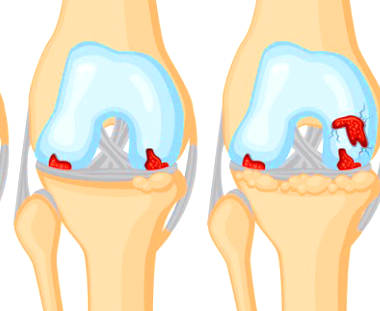

평소 조깅을 하거나 운동을 하면서 무릎에 체중을 싣게 되는데 이럴 때 통증이 지속되면 무릎 연골 손상을 의심해 볼 수 있습니다. 무릎 연골은 허벅지와 종아리뼈 표면을 덮고 있는 일종의 뼈를 보호하는 막으로 무릎 관절을 움직일 때 뼈가 서로 부딪혀 손상되는 것을 막아줍니다.

이런 연골도 나이가 들면 점차 닳으면서 뼈 표면이 노출되고 노출된 뼈는 여러 외부요인으로 자극이 되어 통증을 일으키는데 이것이 바로 퇴행성 관절염이라고 합니다.

이러한 연골은 노화도 원인이 되지만 외부 요인에 의해서 손상이 되고 별 이유 없이 괴사 하기도 합니다. 연골은 한번 손상되면 스스로 재생이 되지는 않습니다. 이를 방치하면 남아있는 연골도 같이 닳아서 관절염으로 진행이 되기도 합니다.